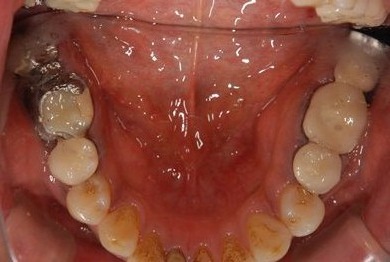

インプラントの症例写真 IMPLANT

インプラント治療+セラミック治療

| 主訴 | 下の奥歯に欠けやブリッジの変形がある。 | ||||||||||||||||||||||||||||||||

| 治療内容 | インプラント2本、メタルボンドセラミッククラウン7本(メタルボンド用土台5本)、歯肉歯槽骨整形手術 | ||||||||||||||||||||||||||||||||